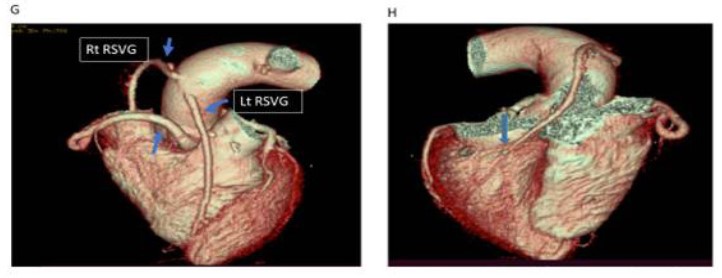

Post-procedural volume-rendered (G &H) CT images show a right main coronary artery (RCA) (plain blue arrow in G), one reversed saphenous vein graft (Rt RSVG) arising from the ascending aorta on the right side (G) coursing inferiorly and anastomosed to PDA (arrow in H). Another reversed saphenous vein graft (Lt RSVG) arising from the ascending aorta on the left side (G) anastomosed to a distal-most portion of the left anterior descending artery (not shown here). Note there is no visualization of the residual fistulous tract (H) between the RCA and left ventricular chamber owing to the successful repair of the coronary cameral fistula.

Figure 4: